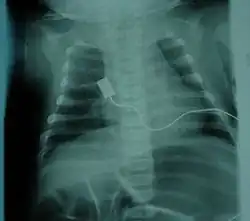

- Bell-shaped torso (caused by using only abdominal muscles for respiration) in severe SMA type